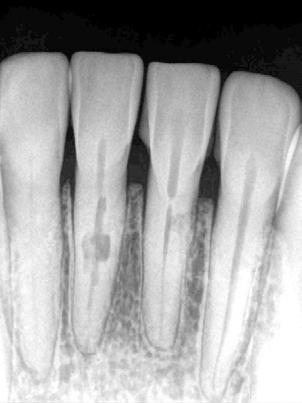

Dientes 31 y 41 - Reabsorción Interna / Conducto obturado con BIO-C® REPAIR. Imágenes cedidas por la Dra. Cimara Barroso.